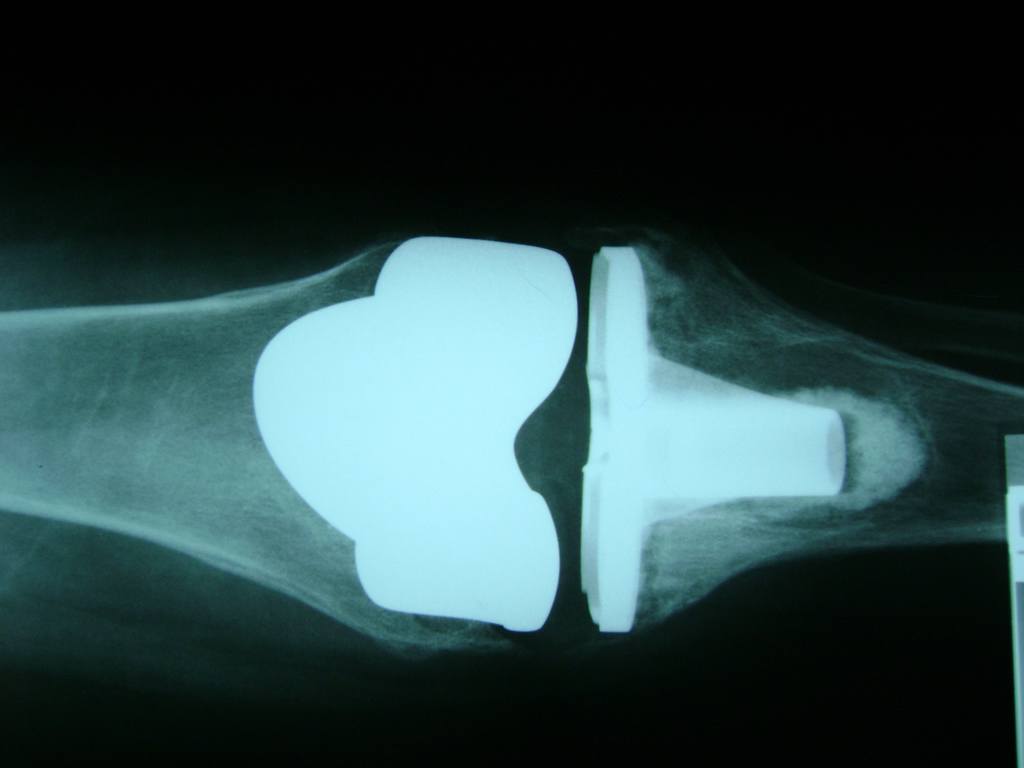

Cirugías de Rodillas